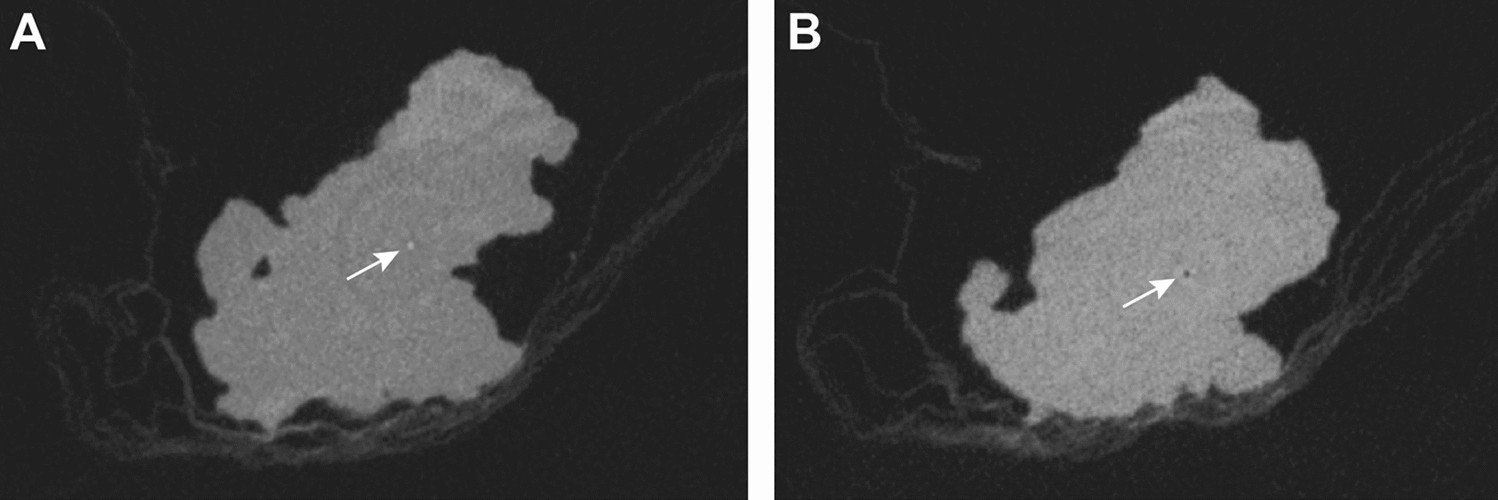

Figure 4

Artifacts in CBCT images of specimens were usually artifacts of the central axis that typically appeared as a central hyperdense spot in some slices (A) and a central hypodense spot in other slices (B) or ring artifacts (A and B).